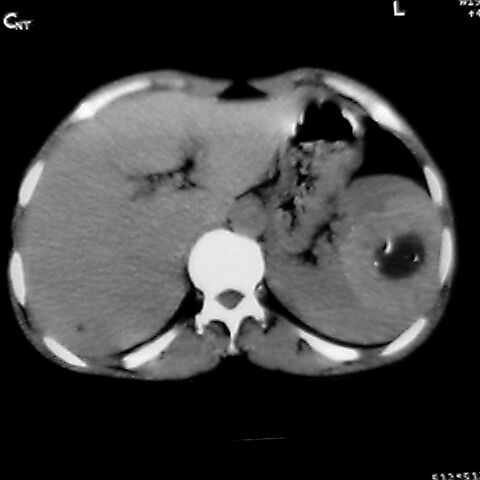

女 48岁 食道癌术前体检发现脾占位。

考虑脾脏血管瘤,中央低密度为血栓形成

脾脏低密度灶伴钙化,增强化明显,中心见液化坏死灶,强化延时明显。考虑血管瘤。转移瘤待排。

1,脾血管瘤。2,右肝,右肾小囊肿。